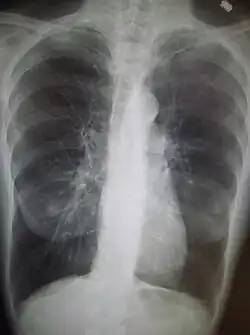

- Radiographie pulmonaire pour les épisodes aigus ;